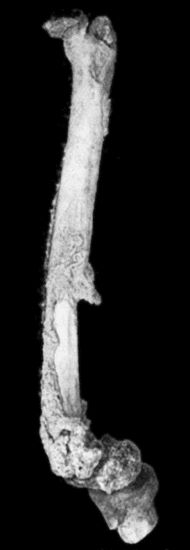

156.Caseating focus in Upper End of Fibula 513